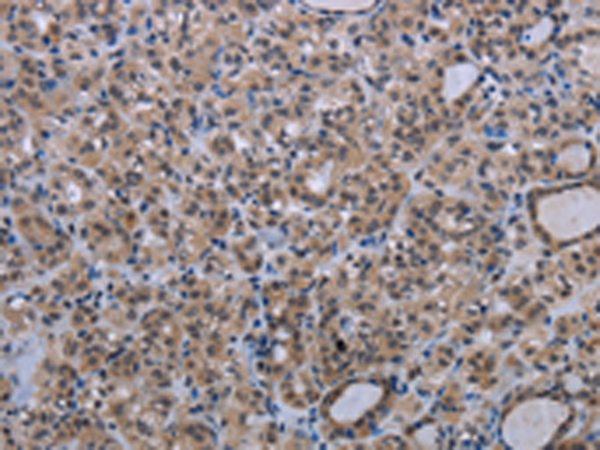

分类: 科研抗体货号: P05121别名:应用: WB,IHC反应种属: Human